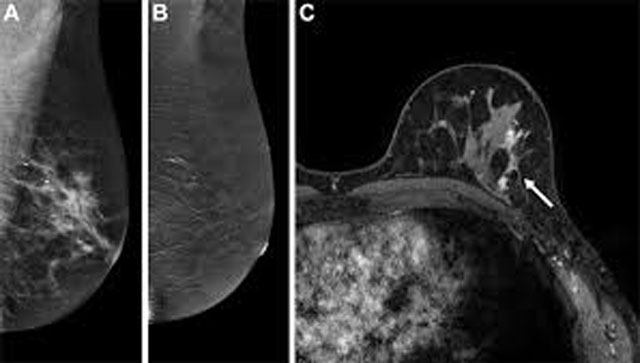

New Delhi, Apr 17: Contrast-enhanced mammography (CEM) demonstrates performance comparable to MRI in assessing tumour size and detecting additional malignant lesions, with closer agreement to histopathology in evaluating disease extent, according to a retrospective analysis.

CEM combines conventional mammography with contrast enhancement to improve visualisation of tumour vascularity. In breast cancer imaging, accurate estimation of tumour size and spread is crucial for surgical planning and identifying multifocal or multicentric disease.

CEM detected 51 of the 52 primary tumours, while MRI identified all cases. Tumour size measurements were nearly identical, with an average of 24.9 mm on CEM and 25.2 mm on MRI, indicating strong correlation between the two methods.

When compared with post-operative histopathology, CEM showed exact agreement in assessing overall disease extent, both averaging 32.6 mm. MRI, however, slightly overestimated the extent, with a mean measurement of 35.0 mm. Larger discrepancies were observed in a few cases, particularly those involving non-mass enhancement, which can be more challenging to interpret.